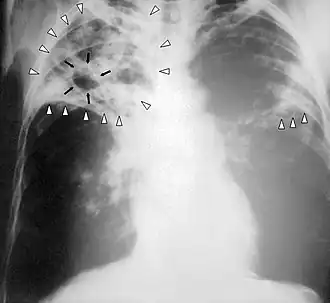

| Chest X-ray of a person with advanced tuberculosis: Infection in both lungs is marked by white arrow-heads, and the formation of a cavity is marked by black arrows. | |

In active pulmonary TB, infiltrates (opaque areas) or scarring are visible in the lungs on a chest X-ray. Infiltrates are suggestive but not necessarily diagnostic of TB. Other lung diseases can mimic the appearance of TB; and this test will not detect extrapulmonary infection or a recent infection.[112]